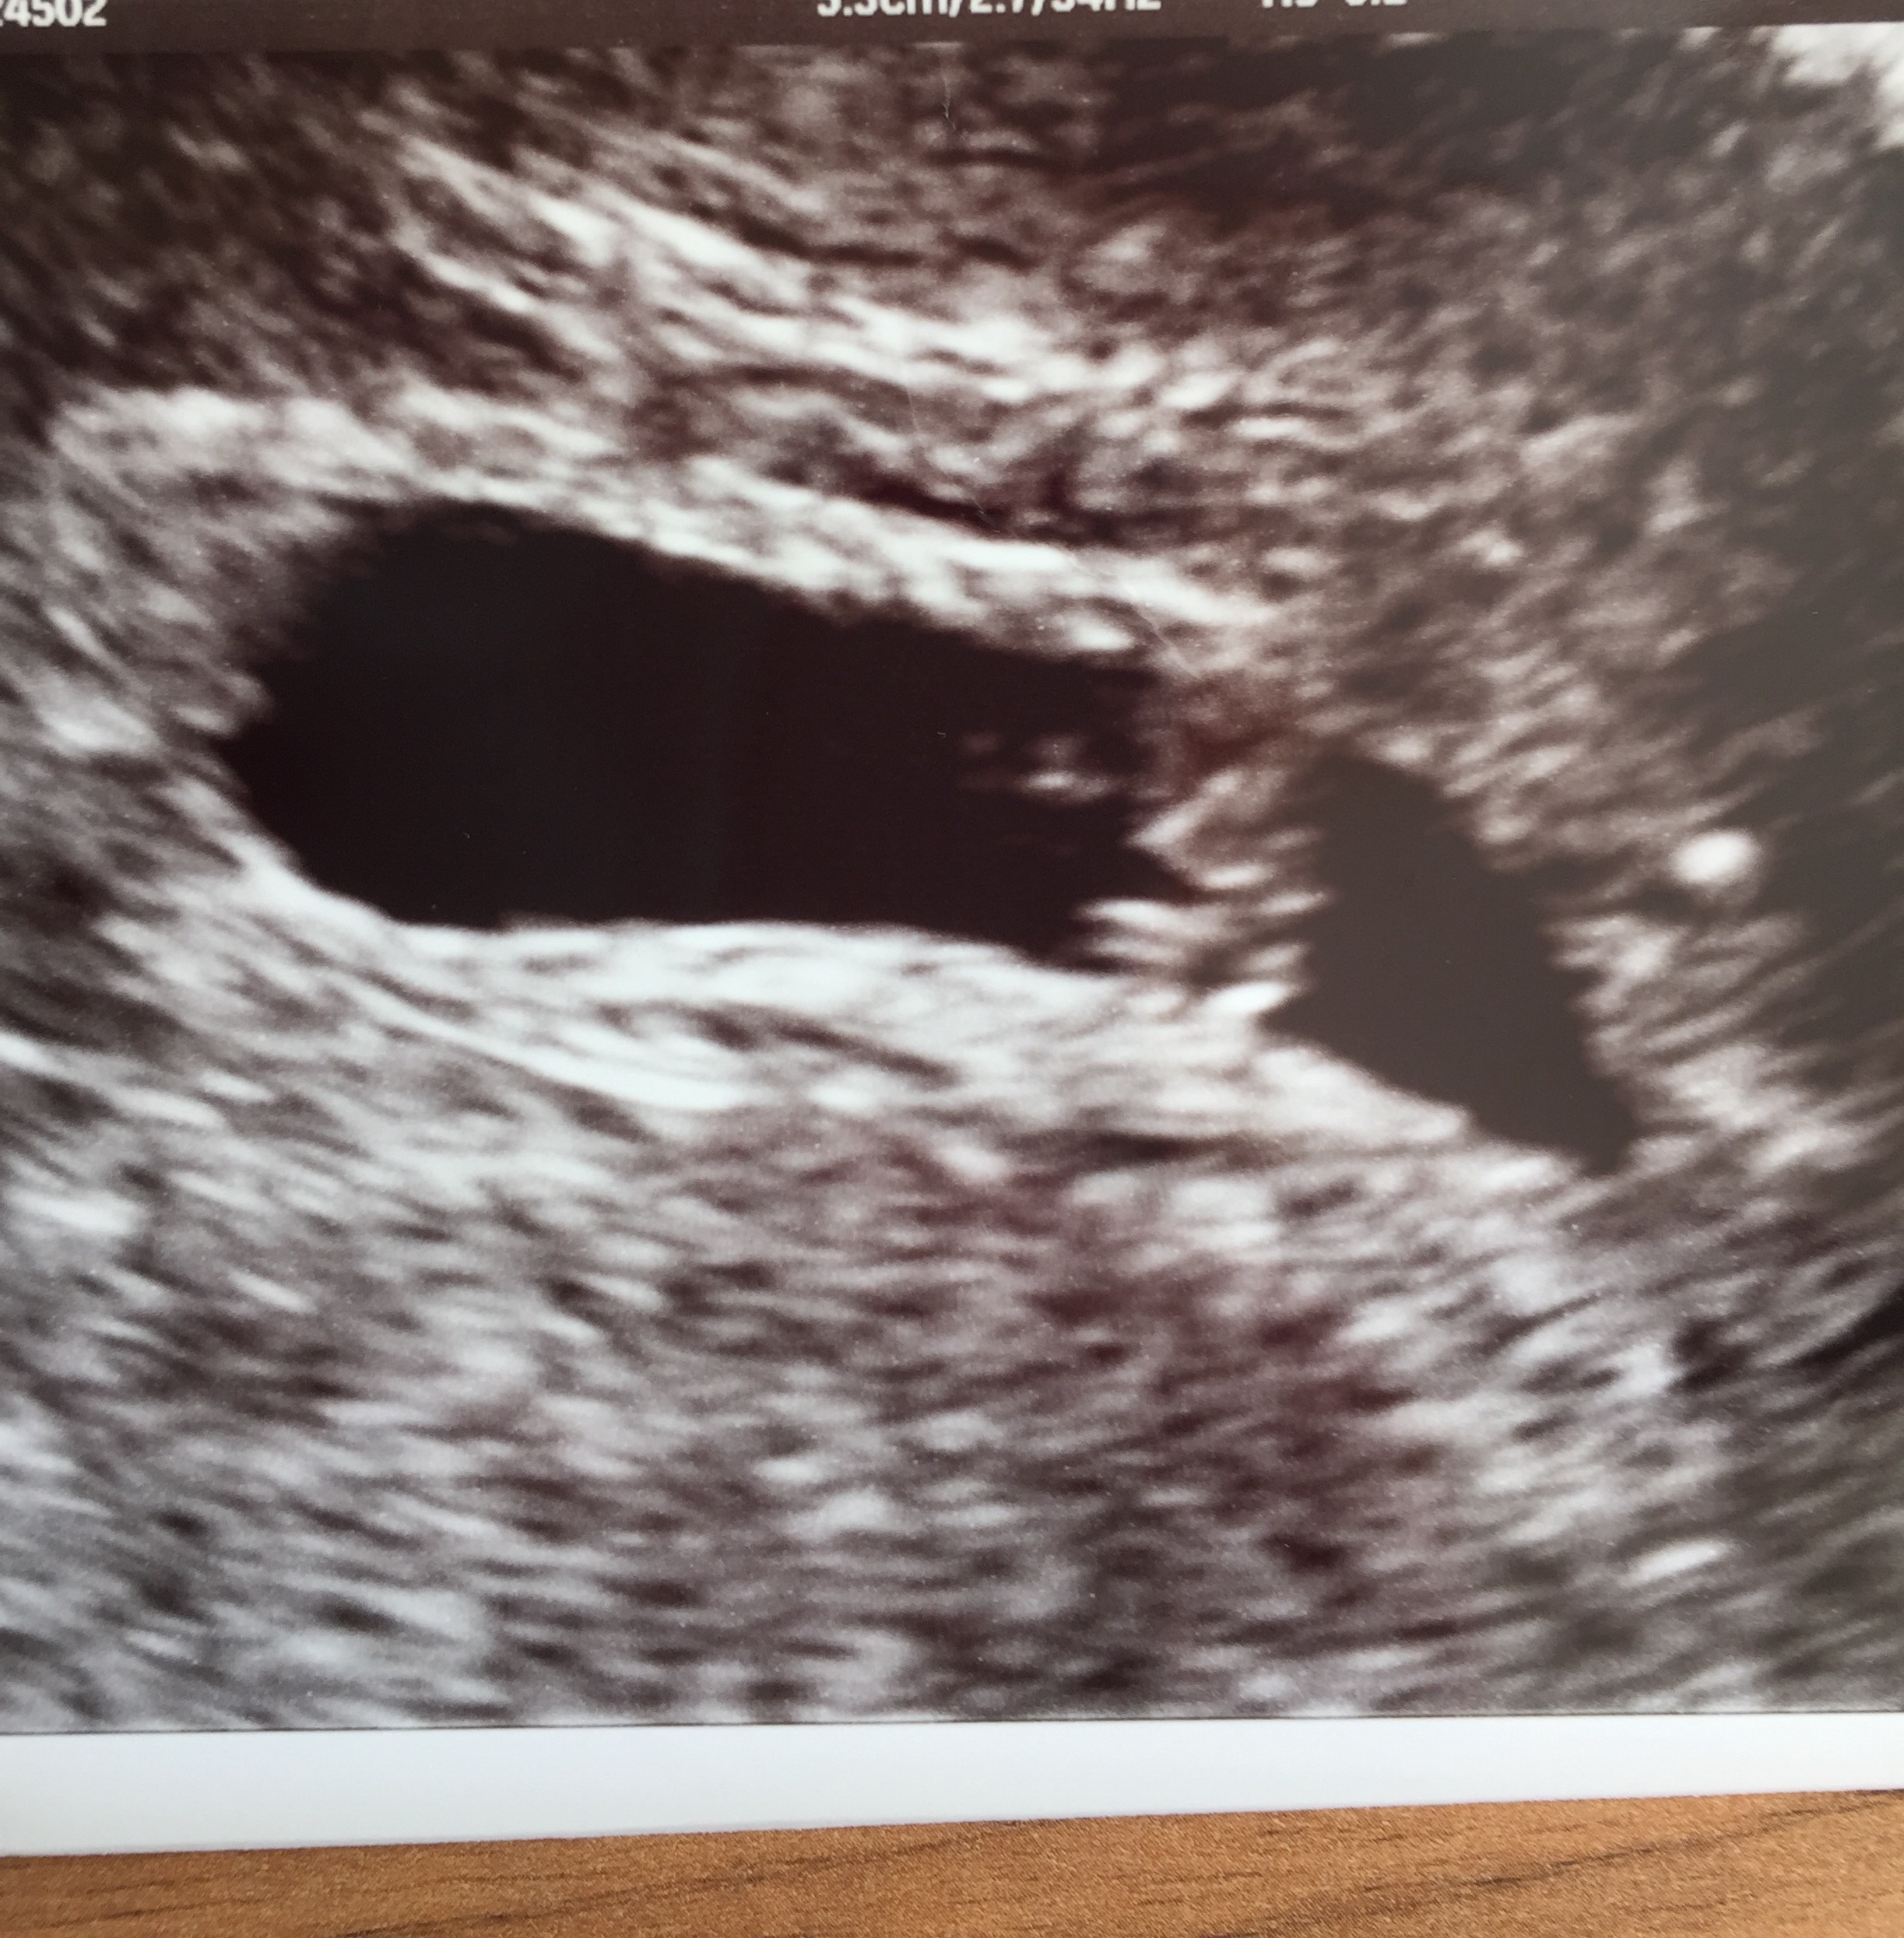

Ramzi guesses for our rainbow baby at 7 weeks 🌈

If this is transvag I guess girl